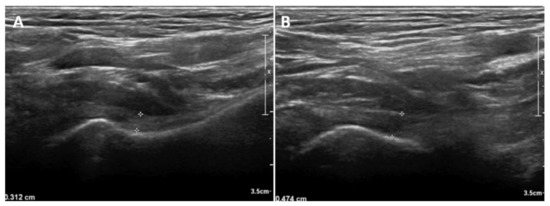

Figure 3.

An illustrative case with unilateral frozen shoulder demonstrating the difference in inferior joint capsule (IJC) thickness in neutral position. (A) IJC thickness of the unaffected side. (B) IJC thickness of the affected side.

In neutral position, the IJC thickness on US was significantly higher in the affected shoulder (mean, 4.04 mm; standard deviation [SD], 1.19; 95% confidence interval [CI], 3.76–4.31) than that in the unaffected shoulder (mean, 2.76 mm; SD, 0.70; 95% CI, 2.59–2.92) (p < 0.001). An illustrative case is shown in Figure 3. In the externally rotated position, the IJC thickness on US was significantly higher in the affected shoulder (mean, 3.15 mm; SD, 1.07; 95% CI, 2.90–3.40) than in the unaffected shoulder (mean, 2.12 mm; SD, 0.50; 95% CI 2.00–2.24) (p < 0.001). In the internally rotated position, the IJC thickness on US was significantly higher in the affected shoulder (mean, 5.92 mm; SD, 1.43; 95% CI, 5.59–6.25) than in the unaffected shoulder (mean, 4.30 mm; SD, 1.24; 95% CI, 4.01–4.59) (p < 0.001) (Table 2, Figure 4).